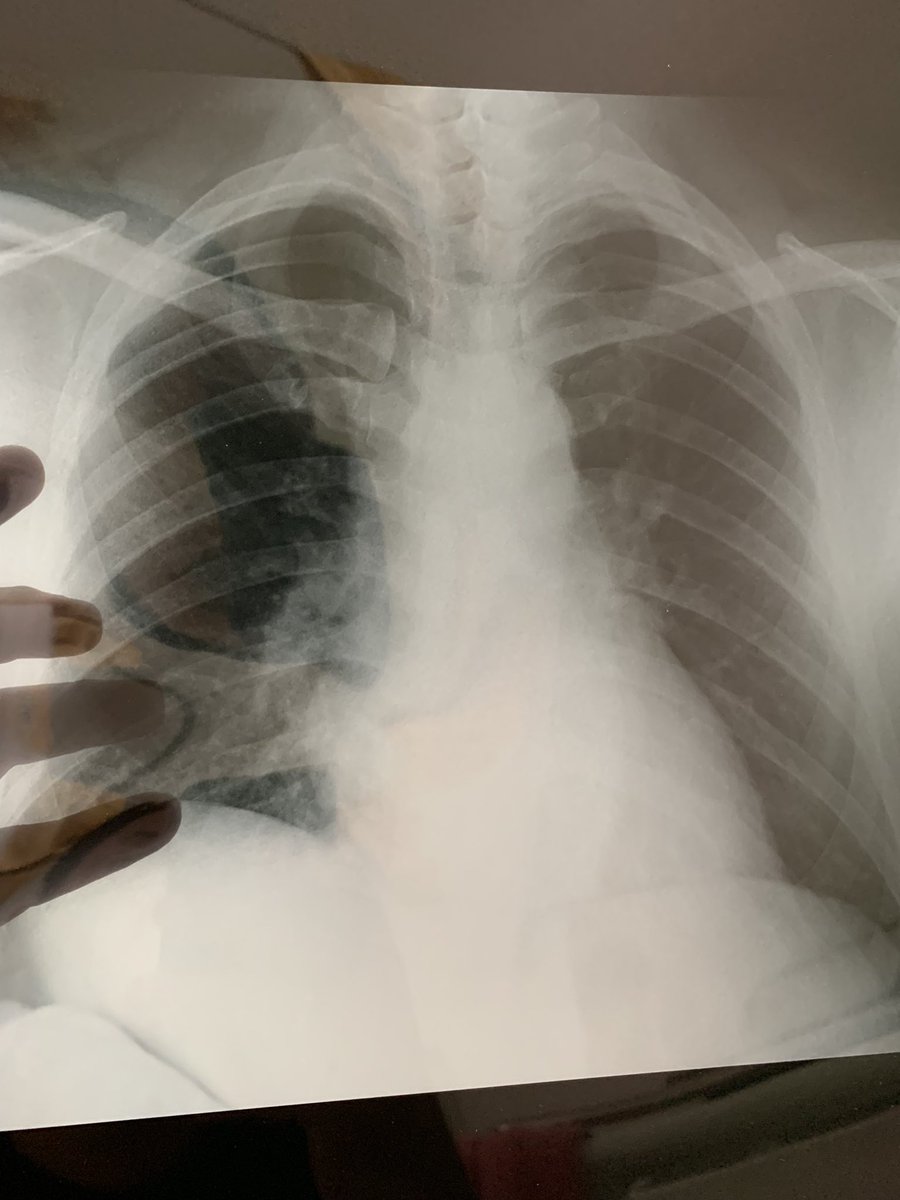

“Heatmaps” covid di paru2 admin (ga ngeroko). Teman2 harus lebih berhati2 lagi krn defend rapat pun jebol. Rontgent ini 3 hari setelah muncul gejala. Mohon maaf jarang update skr dirawat & fokus di kesembuhan.